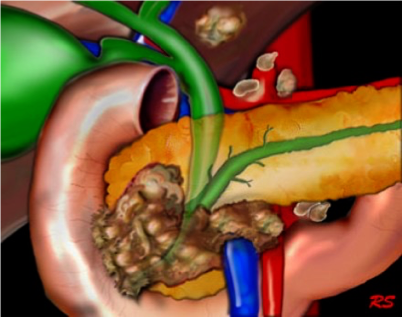

Neoplasms of exocrine pancreas

Malignant tumors

- Ductal adenocarcinoma (the commonest)

- Mucinous cystadenocarcinoma

- Intraductal papillary mucinous neoplasm (IPMN)

- Arise in the head and uncinate process of the pancreas, and they are typically connected to the ductal system of the pancreas.

- IPMNs comprise lesions of the main pancreatic duct, side branches, or a combination.

- The main pancreatic duct is often dilated.

- Contain mucinous fluid which is sometimes extruding from the ampulla of Vater.